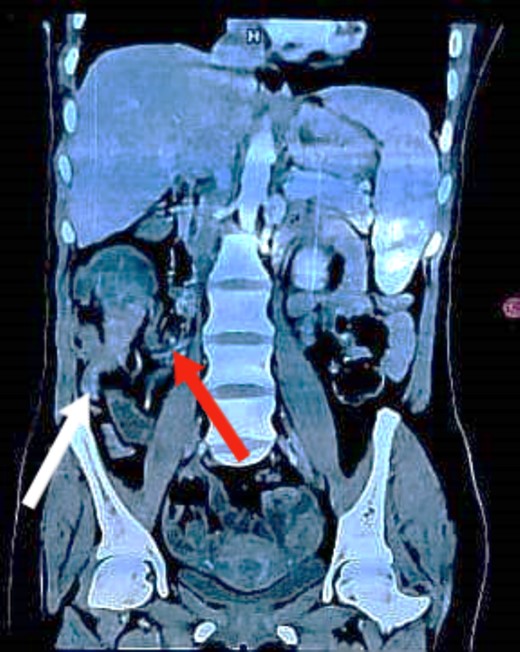

Colonoscopy revealed a malignant-looking mass, the mass appeared irregular, circumferential, fungating and was easily bleeding. It almost occluded the lumen, which correlated with the patient’s symptoms of chronic intermittent intestinal obstruction. The histopathology report indicated invasive moderately differentiated adenocarcinoma. An abdominal CT was conducted and reported a 7 × 5 cm2 soft tissue mass in the ascending colon, highly suspicious for colon cancer, with features of intussusception but no evidence of metastatic disease (Figs 1 and 2). Axial and coronal CT demonstrate the lesion and the intussuscepted bowel].

Coronal CT image demonstrating the lesion with the terminal ileum mesentery inside the cecum. The white arrow indicates the inflamed appendix. The red arrow indicates the terminal ileum and its mesentery entering the cecum.